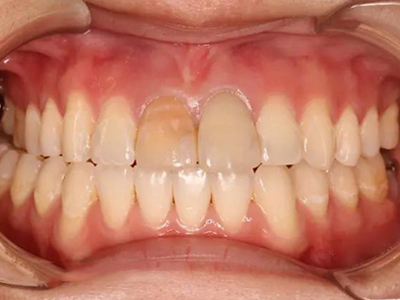

牙釉质发育不全牙上发白图

轻度的牙釉质发育不全患者,牙齿出现色泽和透明度的改变,此时不会影响牙齿的完整形态,也不会导致疼痛不适,仅表现为牙齿上有白色斑点、牙列不齐。

牙釉质发育不全牙齿有白斑图

牙釉质发育不全程度较轻时,导致牙齿表面发白,出现白斑样釉质,导致牙齿透明度下降,同时牙根部位出现棕褐色的带状凹陷,像是没刷牙一样。

牙釉质发育不全牙齿发白长黄斑图

牙釉质发育不全患者牙齿表面发白,呈白垩色,通透性差,部分牙面上出现黄斑,以及小坑和横沟,其内容易积存食物残渣而诱发龋齿,患者无明显疼痛感觉。

牙釉质发育不全牙齿长白斑和黄斑图

牙釉质发育不全表现为牙齿釉质表面出现斑块,呈白斑以及黄斑样,边界不清,形状不一,容易诱发龋病,患者一般无自觉症状,必要时进行修复治疗。

牙釉质发育不全主要表现为牙齿颜色的改变和釉质缺损,可见牙齿呈白垩色改变,光泽度稍差,变得不透明,还可见表面有黄褐色斑块,有轻微凹陷。

牙釉质发育不全牙齿发黄表面有白斑图

牙釉质发育不全会导致牙齿发黄,伴随牙面上出现不透明的白垩状斑块,部分牙齿表面会出现点状、沟状的凹陷,导致牙齿看起来凹凸不平。

牙釉质发育不全表现为白垩色釉质,牙齿看起来很白,没有正常牙齿的通透性,而且牙齿表面常常出现黄斑,呈点片状或者凹坑样,密密麻麻,大致对称分布。

牙釉质发育不全表现为牙齿表面出现黄斑和白斑,白斑呈白垩色,黄斑为淡黄至深黄色,患牙的透明度差,形态正常,无自觉症状,不影响进食。